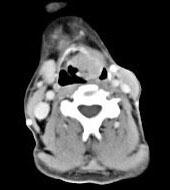

问题 男,53岁,咽部不适半年余,近两个月感咽部疼痛,声嘶,CT如图所示,应诊断为()

选项 A.乳头状瘤 B.喉癌 C.梨状窝癌 D.喉肉芽肿 E.喉部纤维瘤

答案 B